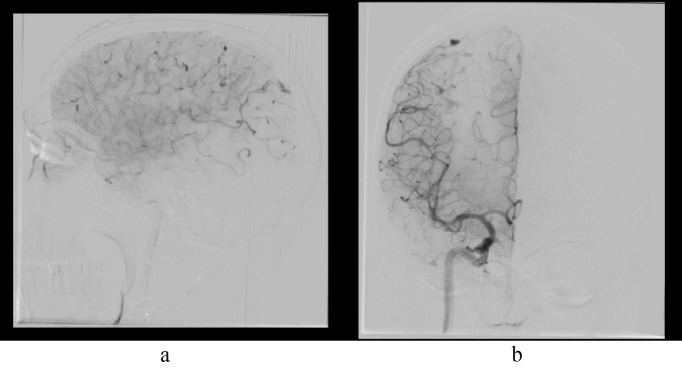

Unforeseen Sequelae: Myxomatous Aneurysm and Cerebral Metastasis in a Case of Atrial Myxoma-A Clinical Image.

不可预见的后遗症:1例心房黏液瘤的黏液瘤性动脉瘤及脑转移——临床影像。